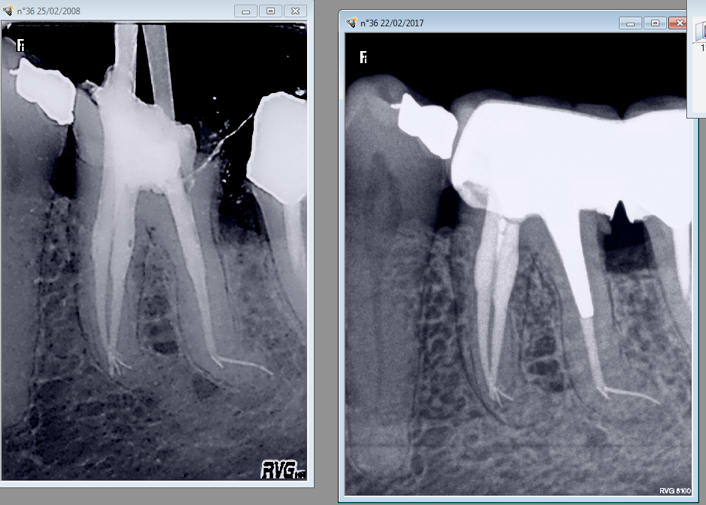

Capture d  cran 2015 03 12 12.28 - Eugenol

chicot29

21/03/2017 à 22h42

Des merdes j'en fais aussi et je les poste aussi d'ailleurs. -)

Tiens en voilà une qui date de 2008 et que j'ai croisée la semaine dernière. Protapers de merde ! -)

Sans digue en plus beurk ! -)

Capture d écran 2017 03 21 22.46 - Eugenol

Tu vas encore nous énerver, même tes merdes se transforment en or :)

Joli le canal distal obturé pile à l'apex courbure négociée, là on peut dire que la meilleur obturation c'est le niti.